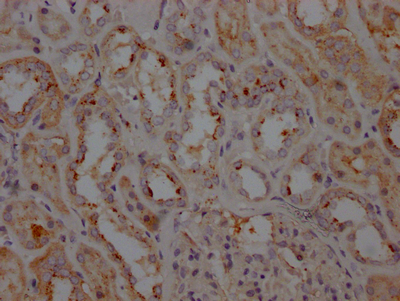

IHC image of CSB-RA797150A0HU diluted at 1:100 and staining in paraffin-embedded human kidney tissue performed on a Leica BondTM system. After dewaxing and hydration, antigen retrieval was mediated by high pressure in a citrate buffer (pH 6.0). Section was blocked with 10% normal goat serum 30min at RT. Then primary antibody (1% BSA) was incubated at 4℃ overnight. The primary is detected by a Goat anti-rabbit IgG polymer labeled by HRP and visualized using 0.05% DAB.